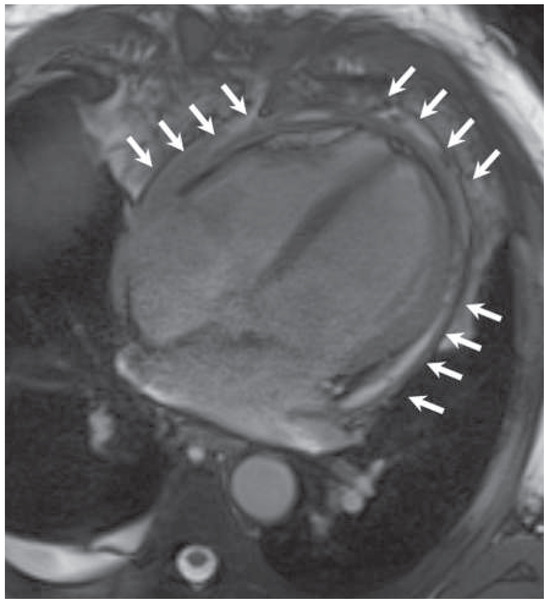

Kussmaul's Sign in Effusive Constrictive Pericarditis

by Mattia Cattaneo, Stefano Muzzarelli, Francesco Faletra, Alessandra Pia Porretta, Francesco Siclari and Augusto Gallino

Cardiovasc. Med. 2015, 18(1), 32; https://doi.org/10.4414/cvm.2015.00296 - 21 Jan 2015

A 67-year old man with mitral valve prolapse and moderate regurgitation was admitted because of dyspnoea, bilateral ankle swelling and hypotension. Close inspection of the jugular veins identified Kussmaul’s sign, a typical increase in the central venous pressure during inspiration (fig. 1; arrows) [...] Read more.

A 67-year old man with mitral valve prolapse and moderate regurgitation was admitted because of dyspnoea, bilateral ankle swelling and hypotension. Close inspection of the jugular veins identified Kussmaul’s sign, a typical increase in the central venous pressure during inspiration (fig. 1; arrows) [...]